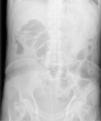

Caso 2Varón de 68 años, colecistectomizado y con una gastroenteroanastomosis tipo Billroth II realizada 20 años antes por un ulcus péptico, con la boca anastomótica permeable en un control endoscópico 3 años antes. Acudió a urgencias por dolor abdominal irradiado a zona lumbar izquierda de 3 días de evolución, acompañado de náuseas, vómitos posprandiales, diarrea sin productos patológicos y anorexia con pérdida de 3-4 kg de peso en el último mes. Refería dispepsia habitual con pirosis y saciedad precoz, que trataba con omeprazol y almagato. En la exploración física el abdomen era blando pero doloroso a la palpación. En una radiografía simple de abdomen se observó un patrón en miga de pan distribuido por el cuadrante superior izquierdo (fig. 1) y en la TC se observó una dilatación gástrica con abundante retención alimentaria sólida compatible con un fitobezoar. Se colocó una SNG en aspiración y se inició tratamiento con metoclopramida i.v. 10 mg cada 6 h y celulasa 5 g al día durante 5 días administrada de la misma forma que en el caso 1. Una EDA realizada a las 24 h de finalizar el tratamiento mostró restos vegetales que formaban una masa de 4 cm de diámetro y de consistencia media, que para eliminarla se fragmentó mediante asa de polipectomía. Tras comprobar ausencia de restos de fitobezoar mediante radiología (fig. 2) se reintrodujo la dieta oral sin complicaciones y se dio el alta a las 48 h de finalizar el tratamiento.